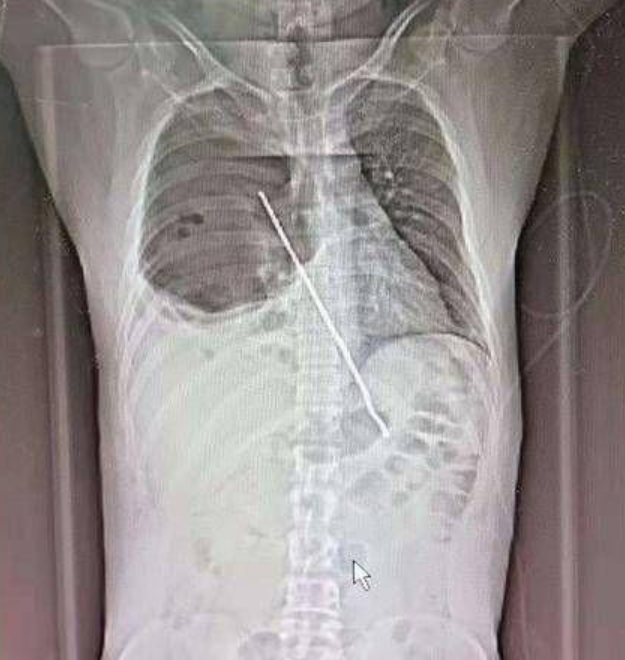

西安医学院第一附属医院急诊科医生接诊后,经行胸部CT及全腹部CT发现长约20cm的铁签穿破小张的食管壁并刺入右肺,右肺胸腔液气胸,右肺挫伤并大部分肺组织不张。急诊医生紧急联系心胸外科会诊,立即入院继续治疗。

当晚23点30分,小张入住西安医学院第一附属医院心胸外科ICU。“因为异物刺激,患者肺部已经感染,呼吸快,频率高,心率也非常高,达到140次/分,氧饱和度很低,氧分压只有39mmHg,已经出现呼吸衰竭的症状。”心胸外科副主任金磊介绍。当务之急,是尽快行胸外手术,将铁签取出。5月11日凌晨3:00,一切就绪,金磊副主任及团队为小张行异物取出术。

手术起初,因考虑开胸手术对患者损伤较为巨大,先行胸腔镜下异物取出,可没想到,患者肺部黏连较为严重,胸腔镜视野不清,遂行全麻下胸腔内异物取出术+肺修补术+脓胸引流清除术。5:45,手术顺利结束。手术取出长约20cm扁平状烤肉铁签,清除胸腔内大量脓苔。